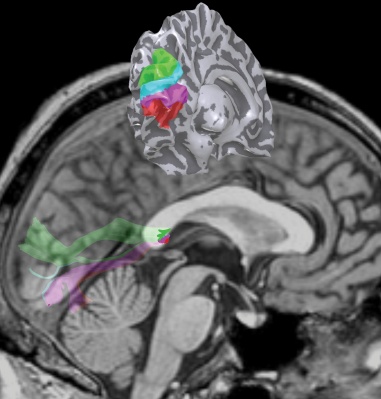

Summary figure from PNAS paper

The left and right hemispheres of the human brain each contain a collection of maps that represent the contralateral half of the visual field. The signals in the left and right hemispheres are coordinated by large bundles of neural fibers that pass through the posterior corpus callosum (splenium). The upper image shows the general location of the maps on the left hemisphere. The background image shows the path of the fiber bundles, as they pass through the splenium and continue to the cortical surface.